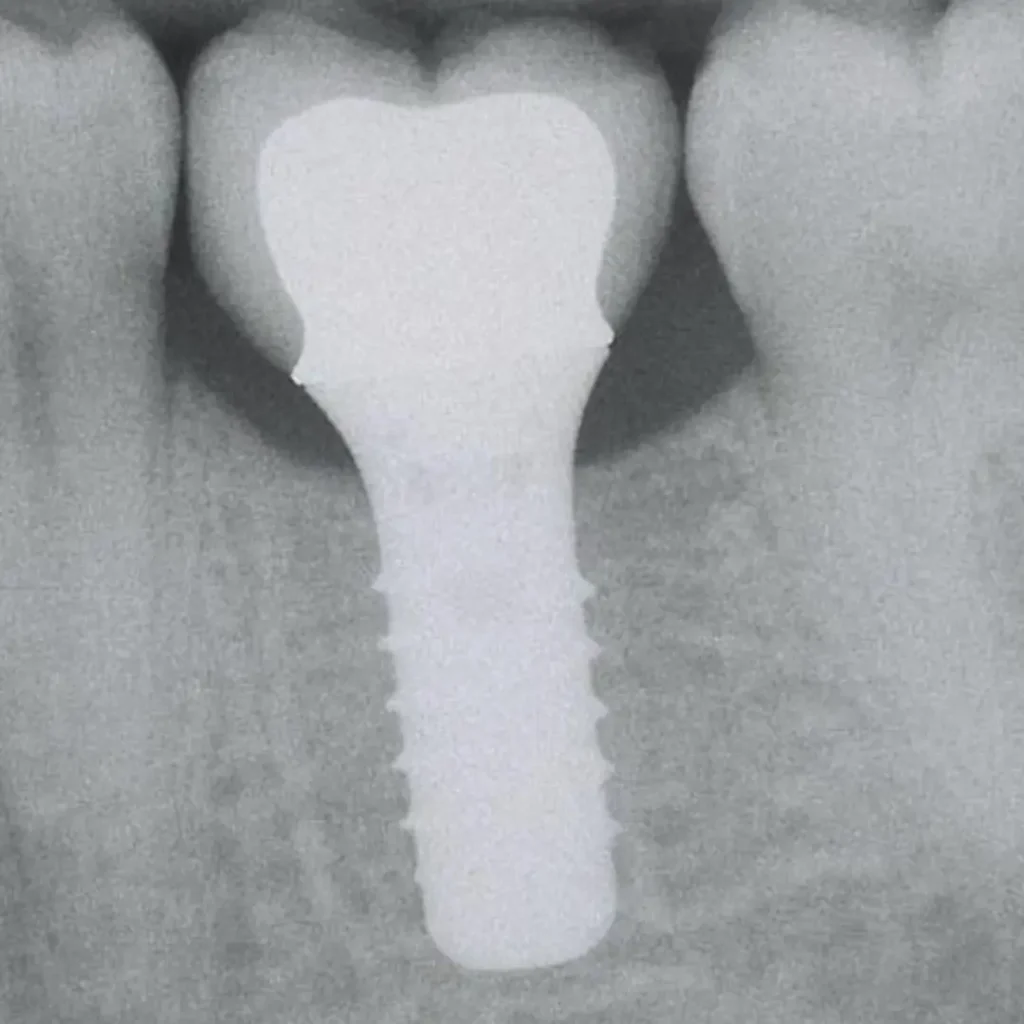

Un implant dentaire est une racine artificielle généralement en titane, que le chirurgien insère dans l’os de la mâchoire à l’endroit d’une dent manquante.

Une fois l’implant posé, il s’intègre solidement à l’os par un processus appelé ostéointégration (le titane fusionne avec l’os sur quelques semaines), ce qui le rend extrêmement stable.

On vient ensuite fixer sur cet implant une couronne prothétique pour remplacer la dent absente.